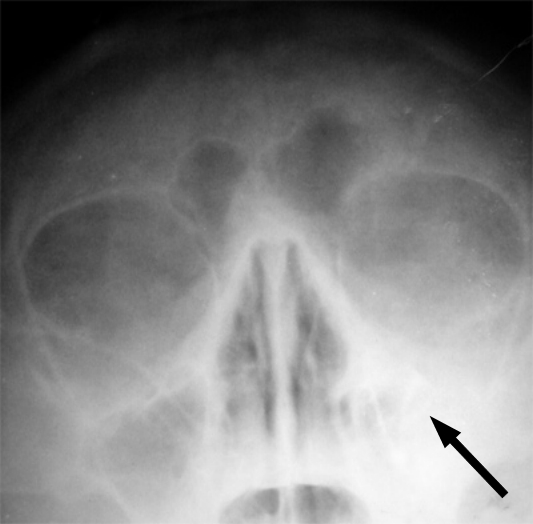

由于患者随后出现单侧头痛、眼窝剧痛及眼皮肿胀,医生警觉安排头部电脑断层扫描(CT),结果震惊所有人:患者右侧多个鼻窦已严重灌脓,感染势力甚至向上刺穿颅骨,在硬脑膜下形成大量蓄脓,导致颅内压飙升,甚至连脑部中线都已被挤压至偏移。